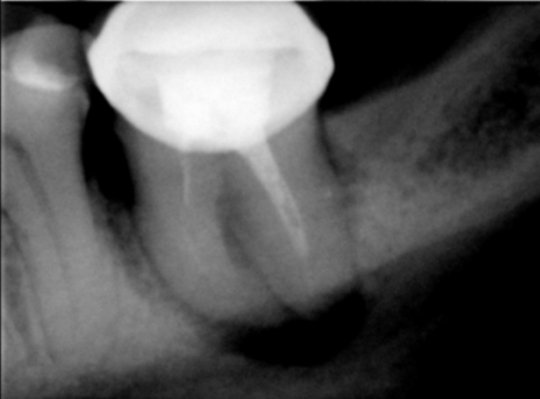

Установлена киста шестого зуба. Указанный зуб пломбировался два года назад.

Подскажите, пожалуйста, можно ли утверждать, что причиной образования кисты стало направильное лечение? Будет ли результат от лечения лазером? И что посоветовали бы вы в данном случае? К/Т зуба:

Причина очевидна, некачественное лечение каналов, да его в принципе нет. Конечно причина кисты именно в этом.